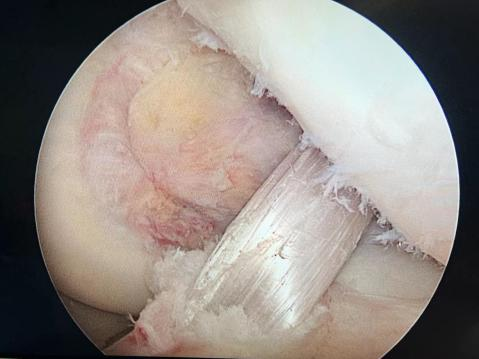

以肩袖损伤的病人为例,很多患者可以进行肩关节镜微创手术来进行治疗,效果非常好。关节镜手术是将具有照明装置的透镜金属管通过很小的切口由自然腔隙进入关节腔内,可以在高清显示器监视下非常直观的观察关节腔内的病变情况和严重程度,全面检查和清理修复病损,是一种兼具诊断和治疗两种功能的微创技术。

运动医学以微创为核心理念,关节镜为主要治疗工具,采用全关节镜下或关节镜辅助下的微创技术,治疗各种运动损伤和退变引起的关节内外相关的疾病以及后期康复。相对于传统切开手术主要有以下优势:1、损伤小,术后疼痛轻,恢复快;2、对关节内结构的观察更全面、更清晰;3、兼具诊断和治疗两种功能。